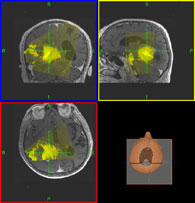

Neurochirurgie MRI Navigation

LOCALITE iMRI Navigator

Der LOCALITE iMRI Navigator ist ein bildgestütztes Navigationssystem. Hauptanwendungsgebiete liegen in Neurochirurgie, HNO und der interventionellen Radiologie. Das System unterstützt interventionell nutzbare Magnetresonanztomographen aller bekannten Hersteller. mehr...